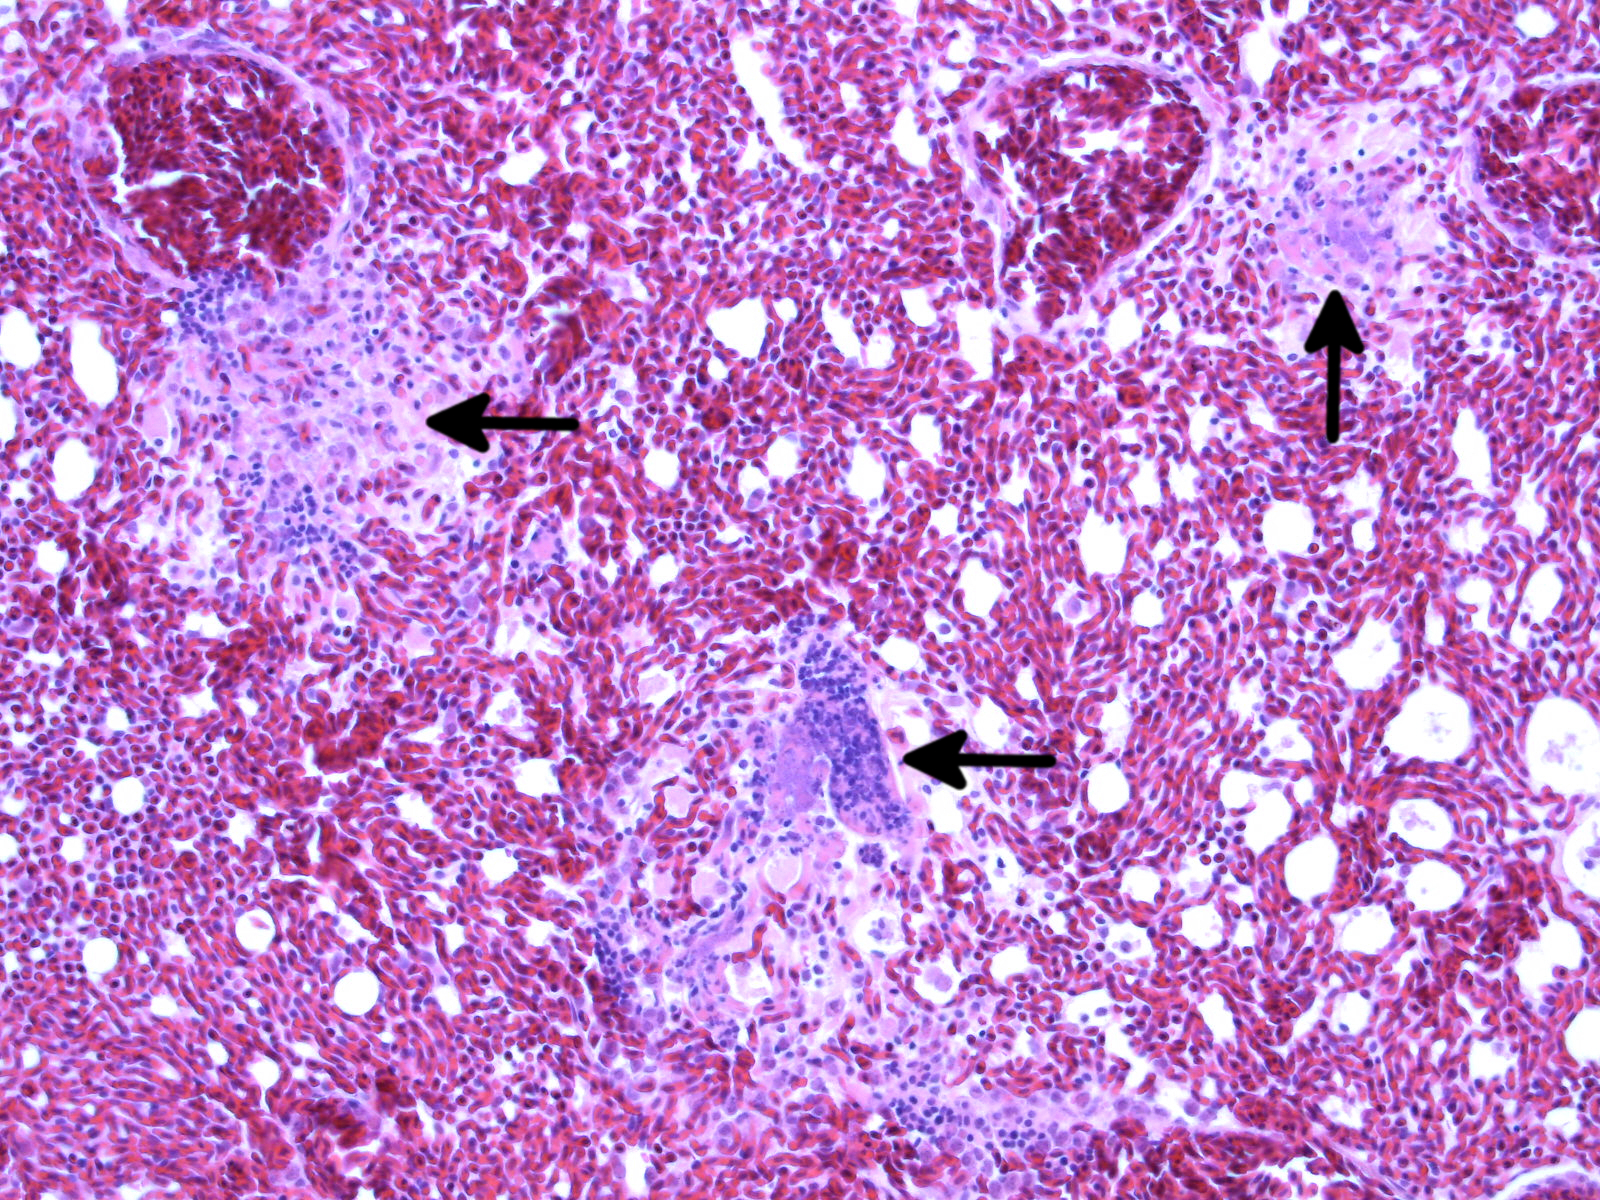

Feingewebliche Aufnahme der Lunge einer Meise. Die Pfeile markieren die deutliche Lungenentzündung bei Tieren, die mit Suttonella ornithocola infiziert waren.

In der Obduktion zeigten die Tiere unterschiedliche Ernährungszustände. Einige Tiere waren gut genährt, während es auch Tiere mit vollständiger körperlicher Auszehrung (Kachexie) gab. Makroskopisch zeigten sich die inneren Organe unauffällig, während feingewebliche Untersuchungen durchweg eine Entzündung der Lunge aufwiesen (fibrinös-nekrotisierende Pneumonie). Auch konnten Bakterienkolonien im Bereich der Entzündungsherde beobachtet werden. Vereinzelt konnte an der Skelettmuskulatur einzelne Zelluntergänge (hyalinschollige Degeneration) beobachtet werden. Bisher (Stand 29.04.2020) wurden 32 Tiere, überwiegend Blaumeisen, untersucht. Bakteriologisch konnte aus den inneren Organen von 16 Tieren das Bakterium Suttonella ornithocola isoliert werden. Bei 10 Tieren verlief diese Untersuchung negativ, 6 konnten aufgrund fortgeschrittener Autolyse nicht entsprechend untersucht werden. Virologische Untersuchungen auf Influenzaviren verliefen negativ.